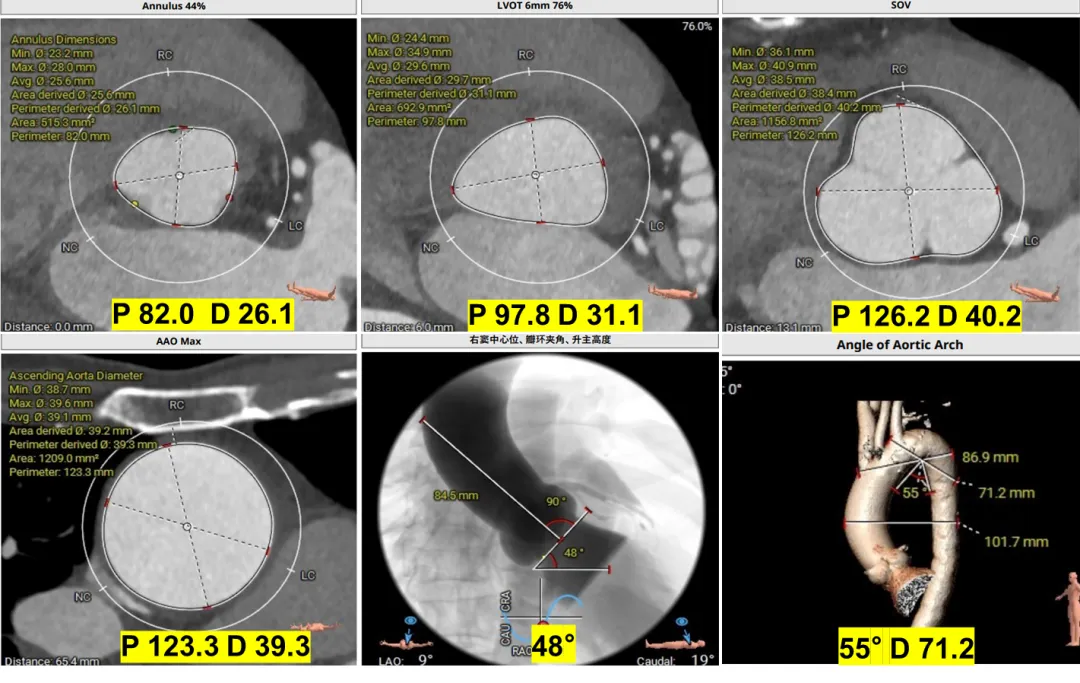

术前CT评估

根据瓣环与 LVOT-6 mm 平面,选择:M 号 TaurusTrio,瓣环可提供7.3%oversize

根据瓣环与 LVOT-6 mm 平面,备后扩解决瓣上,避免瓣周漏,选择:M 号 TaurusTrio